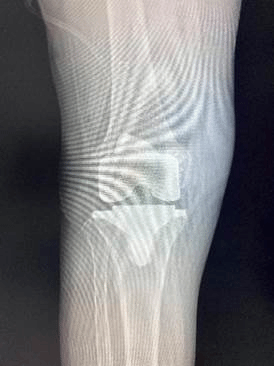

(图六)术后患者X光影相